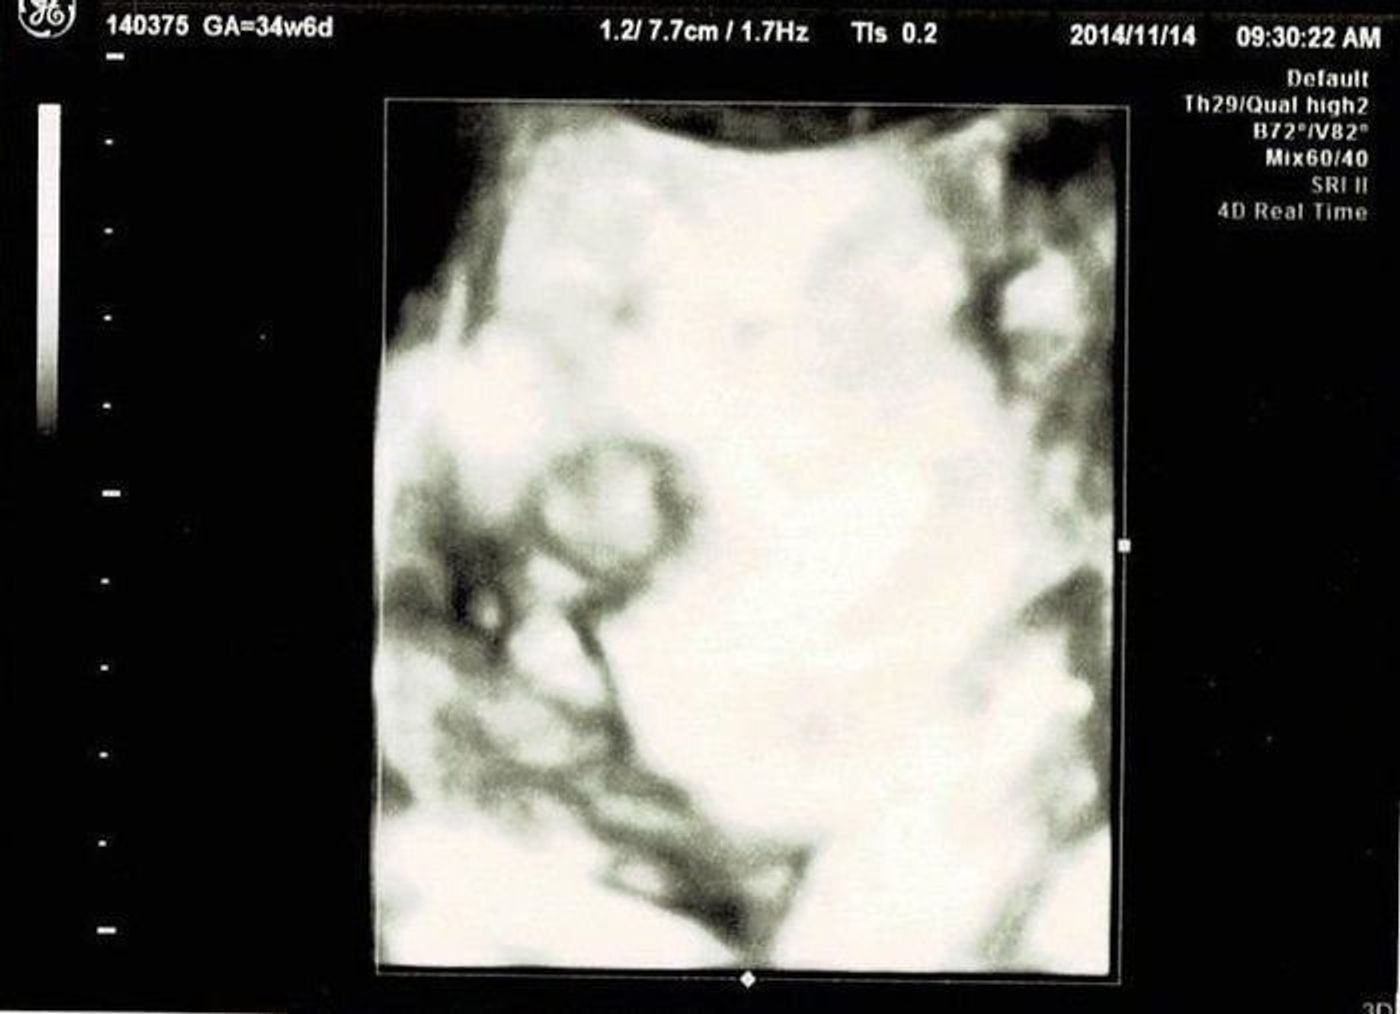

これがよく言う「葉っぱ」なの?? 自分のエコー写真と比べてあーだとかこーだとか よかったらみなさんご意見くださいな~m(_)m お願いします~~~ これは雑誌に載ってる19Wの男の子のエコー写真 確かに矢印状! 赤ちゃんの4Dエコーについて 4Dエコーは冒頭でも説明した通り、動画で赤ちゃんの様子が見られます。 4Dエコーは性別や健康上の問題を見るためのエコーではありません。 赤ちゃんの4Dエコーの料金は? 4Dエコーの料金の相場は5,000〜,000円です。 3D写真 実際、赤ちゃんの